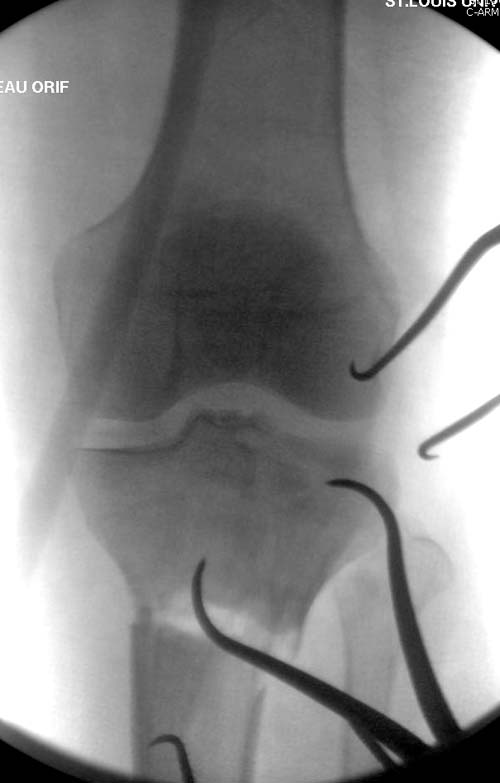

Вытяжение или наружный фиксатор “бедро-голень в виде дельты”. Фиксатор дает свободу, и если условия позволяют, можно отпускать домой. Но главное - надо ожидать проявления “wrinkle sign”! После дистракции можно делать КТ исследование, иначе нестабильные фрагменты искажают данные. Доступ делается по топографии расположения фрагментов, а 3Д картина лучше покажет расположение смещенных мыщелков.

Еще одно дополнение, некоторые в прочтении перелома медиального мыщелка делают типичные ошибки, например, редко переломы медиального мыщелка бывают “только медиальными”, а часто с наличием сложного, заднего компонента, который часто смещается кзади.

На боковом рентгене, явный задний смещенный компонент. КТ поможет увидеть "вершину" перелома, куда надо поставить антискользящую пластину из заднего или задне-медиальнего доступа. Для стабилизации боковой колонны традиционный боковой доступ через Girdle tubercle с длинной блокирующей пластиной. Одна задняя подпорка не удержит медиальную колонну, требуется длинная медиальная пластина.